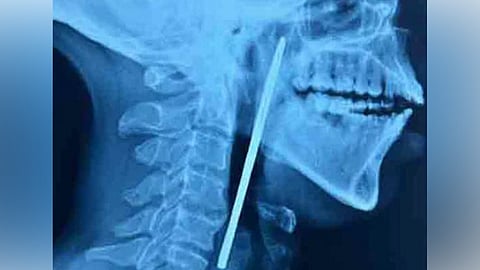

എക്സറേയിൽ അന്നനാളത്തിൽ കത്രിക കുടുങ്ങി കിടക്കുന്നതായി പരിശോധിച്ചപ്പോൾ കണ്ടെത്തി. തുടർന്നു യുവാവിനെ ഇഎൻടി വിഭാഗത്തിൽ പ്രവേശിപ്പിച്ചു. പിന്നാലെ തിങ്കളാഴ്ച രാത്രി നടത്തിയ ശസ്ത്രക്രിയയിലൂടെ 15 സെന്റി മീറ്റർ നീളമുള്ള കത്രിക പുറത്തെടുക്കുകയായിരുന്നു.